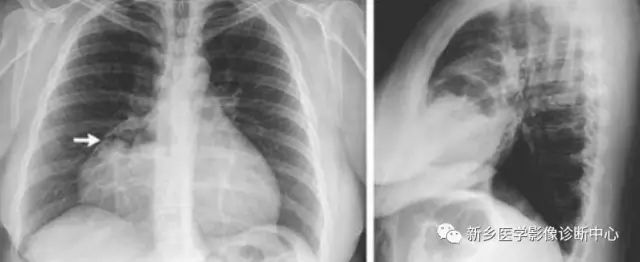

二、Morgagni疝(胸骨旁疝)

胸骨旁疝相对少见,约占膈疝的3%,疝容物多为横结肠。一般无明显症状,偶可形成狡窄。